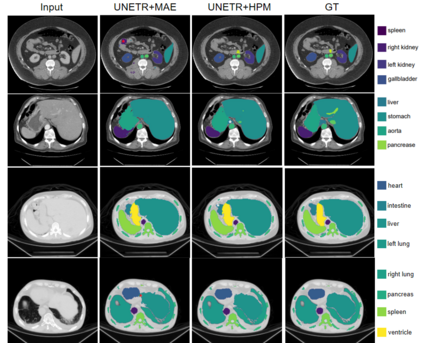

In recent years, deep learning methods such as convolutional neural network (CNN) and transformers have made significant progress in CT multi-organ segmentation. However, CT multi-organ segmentation methods based on masked image modeling (MIM) are very limited. There are already methods using MAE for CT multi-organ segmentation task, we believe that the existing methods do not identify the most difficult areas to reconstruct. To this end, we propose a MIM self-training framework with hard patches mining masked autoencoders for CT multi-organ segmentation tasks (selfMedHPM). The method performs ViT self-pretraining on the training set of the target data and introduces an auxiliary loss predictor, which first predicts the patch loss and determines the location of the next mask. SelfMedHPM implementation is better than various competitive methods in abdominal CT multi-organ segmentation and body CT multi-organ segmentation. We have validated the performance of our method on the Multi Atlas Labeling Beyond The Cranial Vault (BTCV) dataset for abdomen mult-organ segmentation and the SinoMed Whole Body (SMWB) dataset for body multi-organ segmentation tasks.